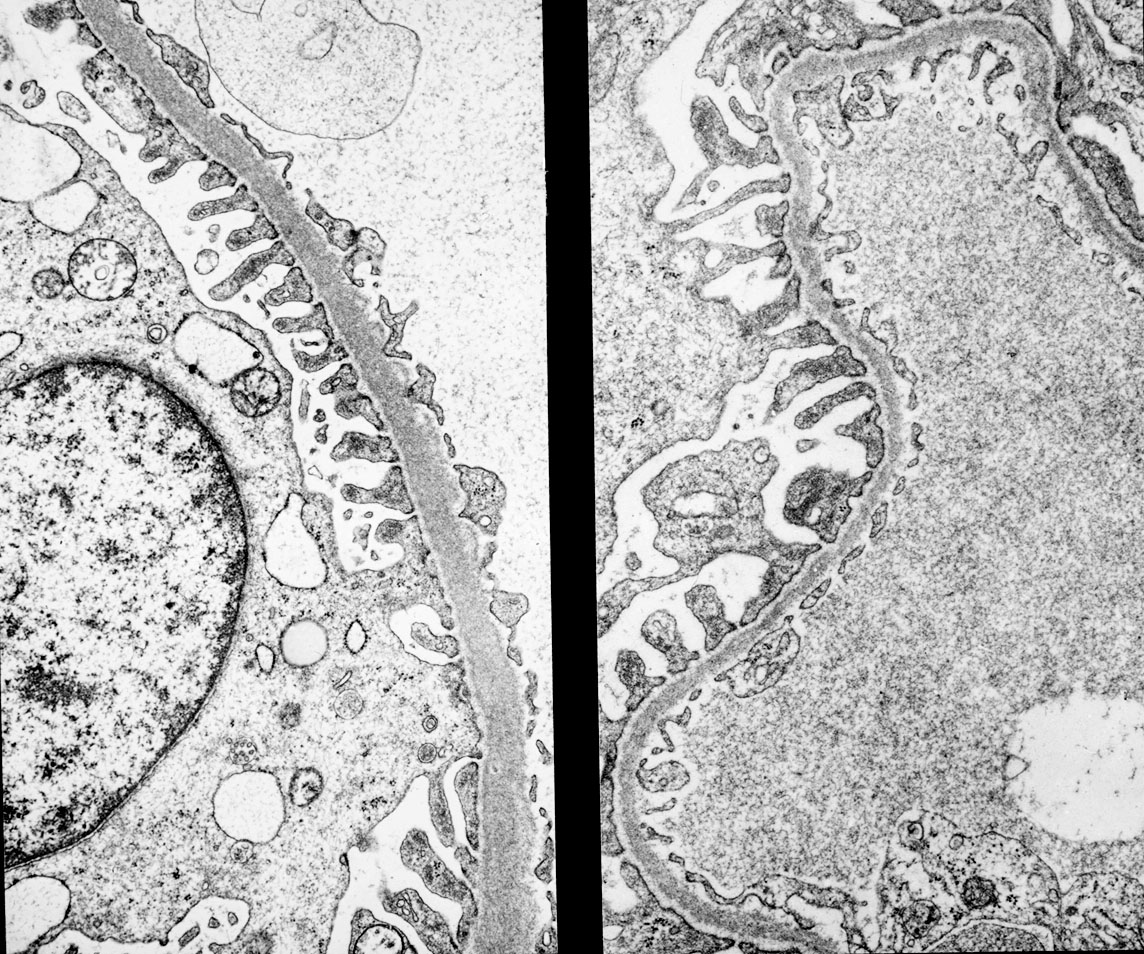

Механизм остро го диффузного гломерулонефрита